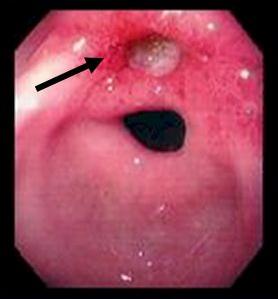

| Image fibroscopique : (A) muqueuse

gstrique normale .(B ) Image gastrite aigue . (C)

Gastrite atrophique .( D ) lesion cancereuse

|